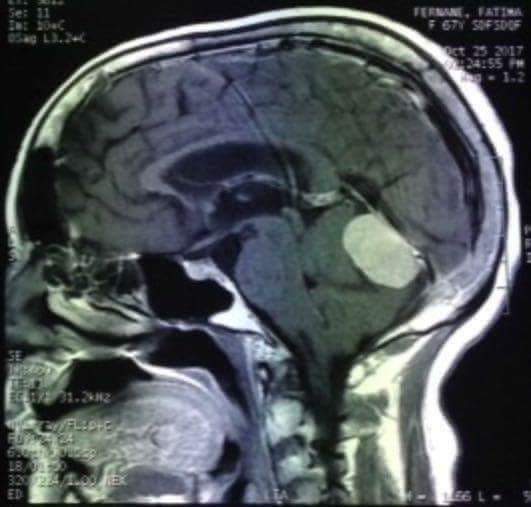

أجريت يوم الإثنين 13 من شهر نونبر بالمستشفى الإقليمي لخنيفرة عملية جراحية الأول من نوعها بجهة بني ملال خنيفرة المتمثلة في إستئصال ورم داخل الحفرة الخلفية من الدماغ لمريضة تبلغ من العمر 60 عام ، حيث دامت العملية لمدة 11 ساعة بالمركب الجراحي للمستشفى، وتعتبر هاته العملية الأولى من نوعها على الصعيد الإقليمي بالمغرب بإعتبارها عملية معقدة ودقيقة وتصنف من أصعب العمليات في هذا التخصص ( جراحة الدماغ والعمود الفقري ) وتجرى مثل هاته العمليات غالبا على مستوى المستشفيات الجامعية لصعوبة إجرائها.

هذا وتكللت العملية الجراحية بالنجاح حيث تم إستئصال الورم بنسبة 100% كما ان المريضة في حالة جيدة و مستقرة. لينفرد المستشفى الإقليمي بخنيفرة بهذا الإنجاز كأول عملية مماثلة تقام بمستشفى إقليمي على الصعيد الوطني .